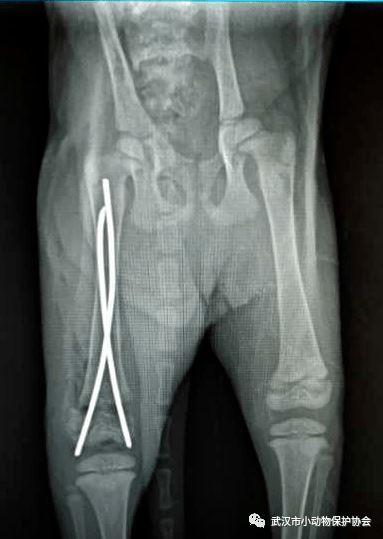

卓刀泉一小区的业主联系协会,她救助了一只后腿受伤的小猫,自己送往医院检查,医生预估手术费用较高,她无力承担,然后联系到了协会,经过沟通商议,她表示可以出猫咪一部分的费用。

小橘猫的骨折比较严重,手术矫正恢复良好,两周后顺利出院。小橘猫接受领养。小橘猫的手术和住院费用是1800元,救助人承担了800,还有 1000元空缺。